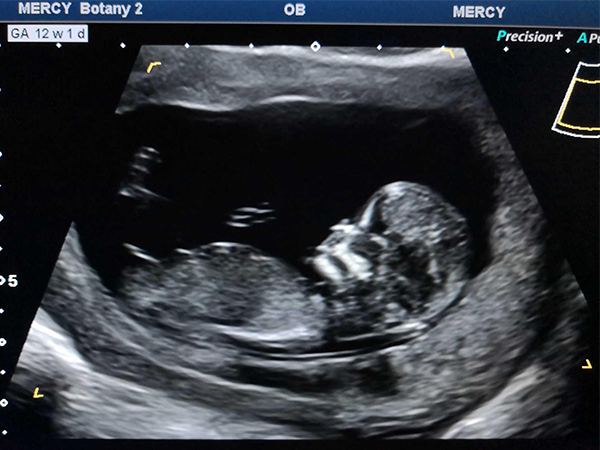

孕期很多爸爸妈妈们都想知道胎儿的性别,除了常规的b超检查单以及各种胎梦来推断胎儿性别之外,很多人都认为从nt检查时胎儿的姿势中就能看出是男孩还是女孩,一般认为如果..

nt检查是孕11~14周后孕妈到医院做的一项排畸检查,这项检查又称为颈项透明层扫描。nt检查除了用于排查畸形,有的人还通过nt检查来判断胎儿性别。一是如果nt值大于1.5的话男..

nt图弯着就是男孩!这些nt看男女诀窍建议收藏!nt检查是孕11~14周后孕妈到医院做的一项排畸检查,这项检查又称为颈项透明层扫描。nt检查除了用于排查畸形,有的人还通过nt..